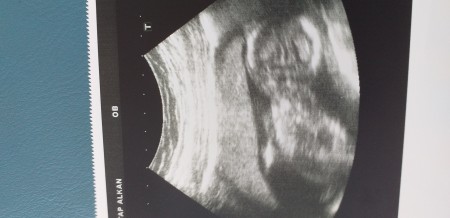

Kızlar yeni hastaneden geldim bebeğim ters ve poposunun üstüne oturduğu için görmedik tahmini olan var mı

Gebelik haftası 16+4

Nub teorisi  bebeğim  cinsiyetini oluşturduğu yer cnaim   eğer nup teorisine göre  12  haftada  ve sonrası  bi çıkıntı  var  sa  erkektir  eğer  bi çıkıntı  görünmez  ise  kızdır  canım  niye  sordun  bu soruyu şimdi  ben  saten  pozisyon uygun ise  o çıkıntıyı  gördüm  ise erkek  diyorum  bumu doktorlarda  aynı  bide  kemik  yapısı  var onlar  iyce yakınlaştırıp  bakıyorlar  popo  kısmında bi kemik  var o yukarı ise  erkek  düz  ise kız   doktorlar  kemik  yapısına gör  rahmi napiyor   ve çıkıntı  görürse erkek diyor   ve bu  plesenta  olabiliyor  bazen ama  orda çıkıntı yok sa  kız dır  bellidir  saten   ben  kese  ve şekline bence  bakıp  vermiyorum  bacak  arası  boş mu  çıkıllnti varmı  buna  göre  bakıp söylüyorum

Ve  ikinci  fotoda  ise    bacak  arası  çekmiş  dilaltı  bakımca sanki çıkıntı  var  ama  ilk başta bi şişlik oluyormuş   ekrem  gib i görünüp sonradan düşemiyormuş  düze  donuyormus benim  tahminim  erkek  olduğunu  düşünüyorum   cnaim  doktora gidince öğrenin  ce yaz

Orda  bi çıkıntı   var  sanki  erkek   gibi  canım  isaretledim  pipi  gördüğüm yeri

Aslinda erkek  diyorum

imagebu daha yakın bir fotoğraf

Evt  canım  erkek  erkek  bu kesin

Ters olduğu için  ben pek göremiyorum :))